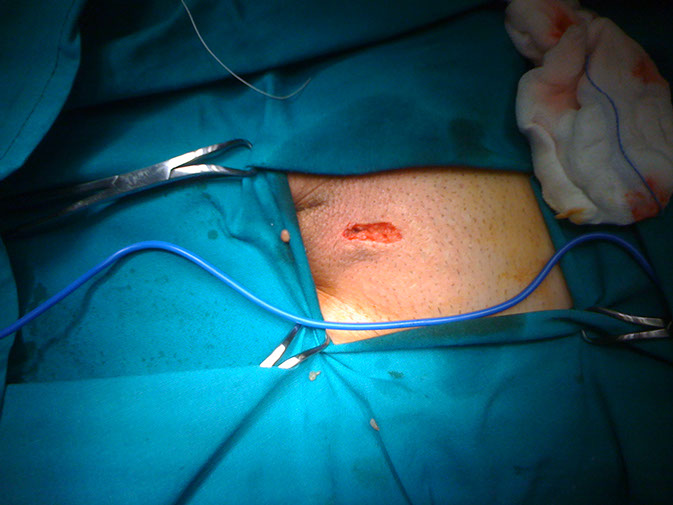

Ο κ Φατλές εφαρμόζει την μικροχειρουργική τεχνική για την αποκατάσταση της κιρσοκήλης τα τελευταία 8 χρόνια με ιδιαίτερα υψηλά ποσοστά επιτυχίας. Η βουβωνική τομή που γίνεται είναι περίπου 2-3 εκ. και ο ασθενής συνήθως φεύγει από το νοσοκομείο την ίδια ώρα. Η επάνοδος στις δραστηριότητες μπορεί να γίνει μετά από δύο μέρες.

Χειρουργική τομή για μικροσκοπική αποκατάσταση κιρσοκήλης σε ασθενή του κ Φατλέ.